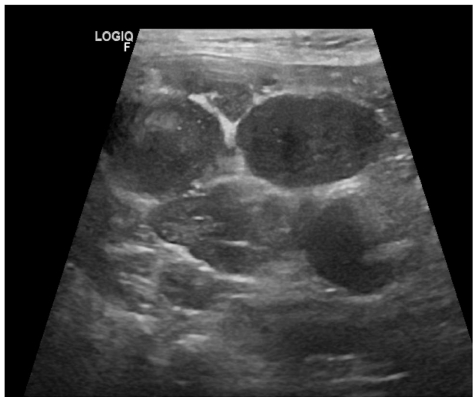

本刊推荐:针对犬类全身性淋巴结病变易误诊为淋巴瘤的问题,研究人员通过一例迷你雪纳瑞犬的临床案例,开展鸟分枝杆菌复合体(MAC)感染模拟恶性肿瘤的鉴别诊断研究。通过细胞学染色、分子鉴定(GenoType Mycobacterium CM)及药敏测试,确诊MAC感染并调整治疗方案(克拉霉素替代利福平)。结果强调齐尔-尼尔森染色在细胞学检查中的关键作用,揭示迷你雪纳瑞犬可能存在CARD9基因相关的免疫缺陷易感性。该研究为罕见人兽共患病的精准诊疗提供重要参考,发表于《BMC Veterinary Research》。